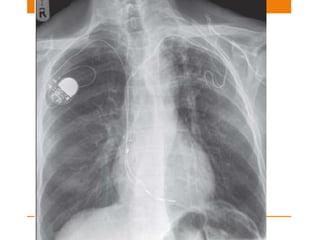

Pacemaker

SINGLE OR DUAL CHAMBER

Single chamber –nowadays used less frequently

• used for atrial or ventricular dysarrythmia

• Atrial – positioned in right atrial appendage

• Ventricular – Electrode placed against myocardium at

apex of right ventricle

Dual pacemaker

• Attempts to synchronize atrial and ventricular system

• One electrode @ Right atrium

• Other electrode @ apex of right ventricle

Sometimes a third lead is also noted

• Third –coronary sinus <Biventricular pacing>

Misplaced Leads

Complications

• Myocardial penetration – if electrode tip is within 3mm

of epicardial fat

• Myocardial perforation – if tip is in epicardial fat

• Pneumothorax

• Pleural effusion